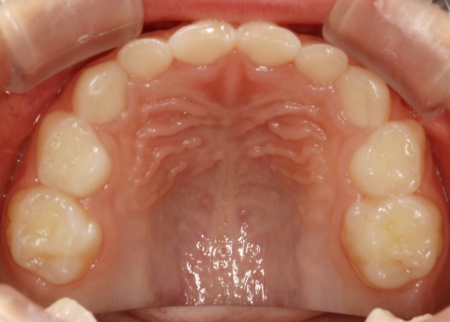

まずは上顎に「バイオブロック(BB1)」という装置を装着します。

バイオブロックとは、上顎の骨を前方に成長させることを目的とした、乳歯列期のお子様に適した矯正装置です。この装置により、上顎の骨の成長を促して反対咬合の改善を図りました。

続いて下顎には、顎の幅を広げて歯が並ぶスペースを確保しながら、上下の噛み合わせのバランスを整える役割をもつ「拡大床」という装置を装着しました。